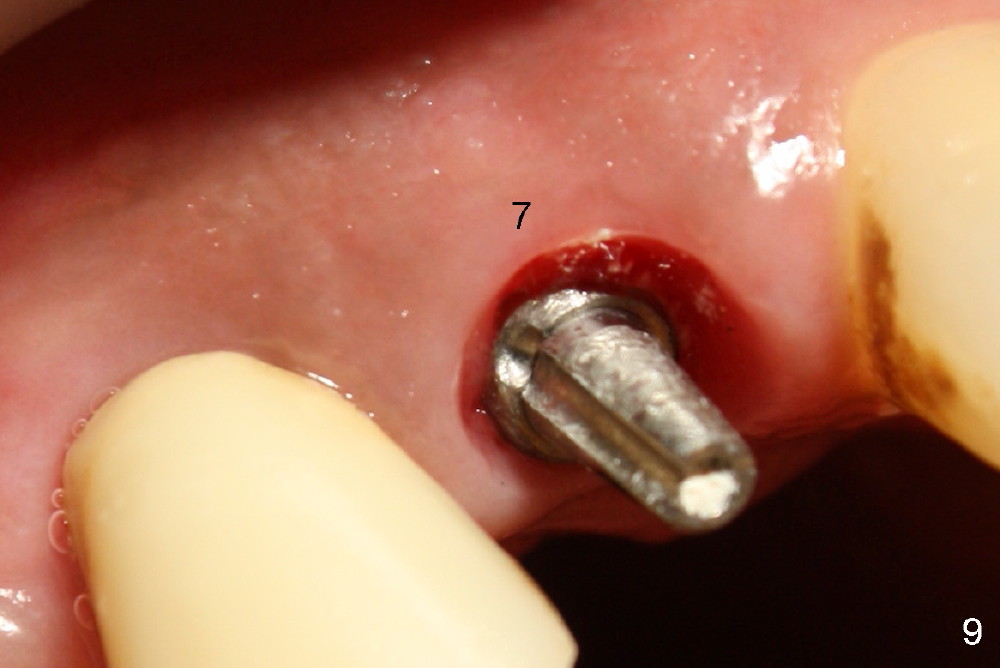

Fig.9 (magnified): Retention groove of the implant and abutment at the site of the tooth #7, one month and a half post immediate implant and immediate provisional.